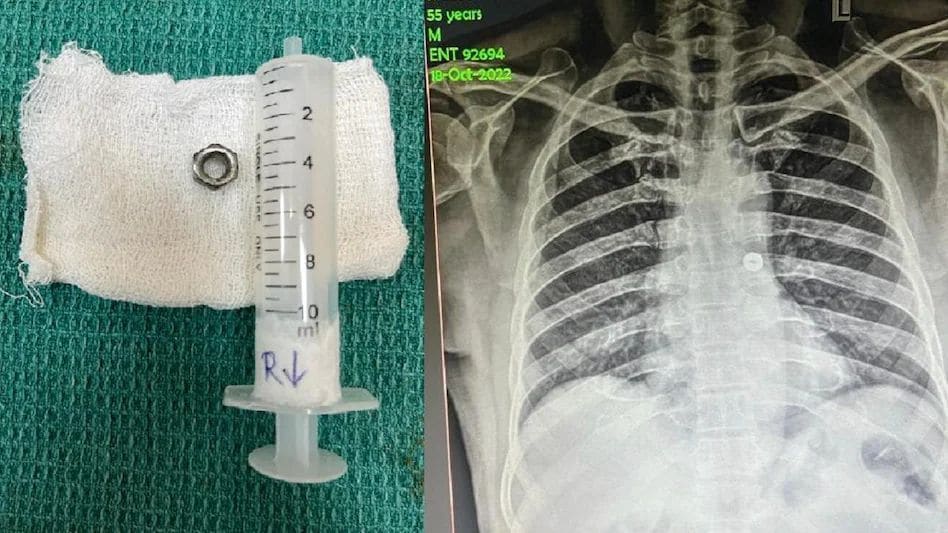

ये घटना है तमिलनाडु में कोयंबटूर की है। शमशुद्दीन नाम का शख्स इलेक्ट्रिशियन का काम करता था। 18 अक्टूबर को काम करते हुए उसने गलती से एक लोहे का नट निगल लिया। बताया जाता है कि उसने उसे खांसकर बाहर निकालने की कोशिश की, लेकिन ये संभव नहीं हुआ। आनन फानन में उसे सरकारी अस्पताल में भर्ती कराया गया।

डाक्टरों ने उसका एक्स-रे किया। उसमें डॉक्टरों ने देखा कि नट उसकी सांस नली में अटका हुआ था और उसके बाएं फेफड़े की ओर जा रहा था। बिना समय व्यर्थ किए डाक्टरों ने शमशुद्दीन का ऑपरेशन किया और नट को सफलतापूर्वक निकाल दिया।